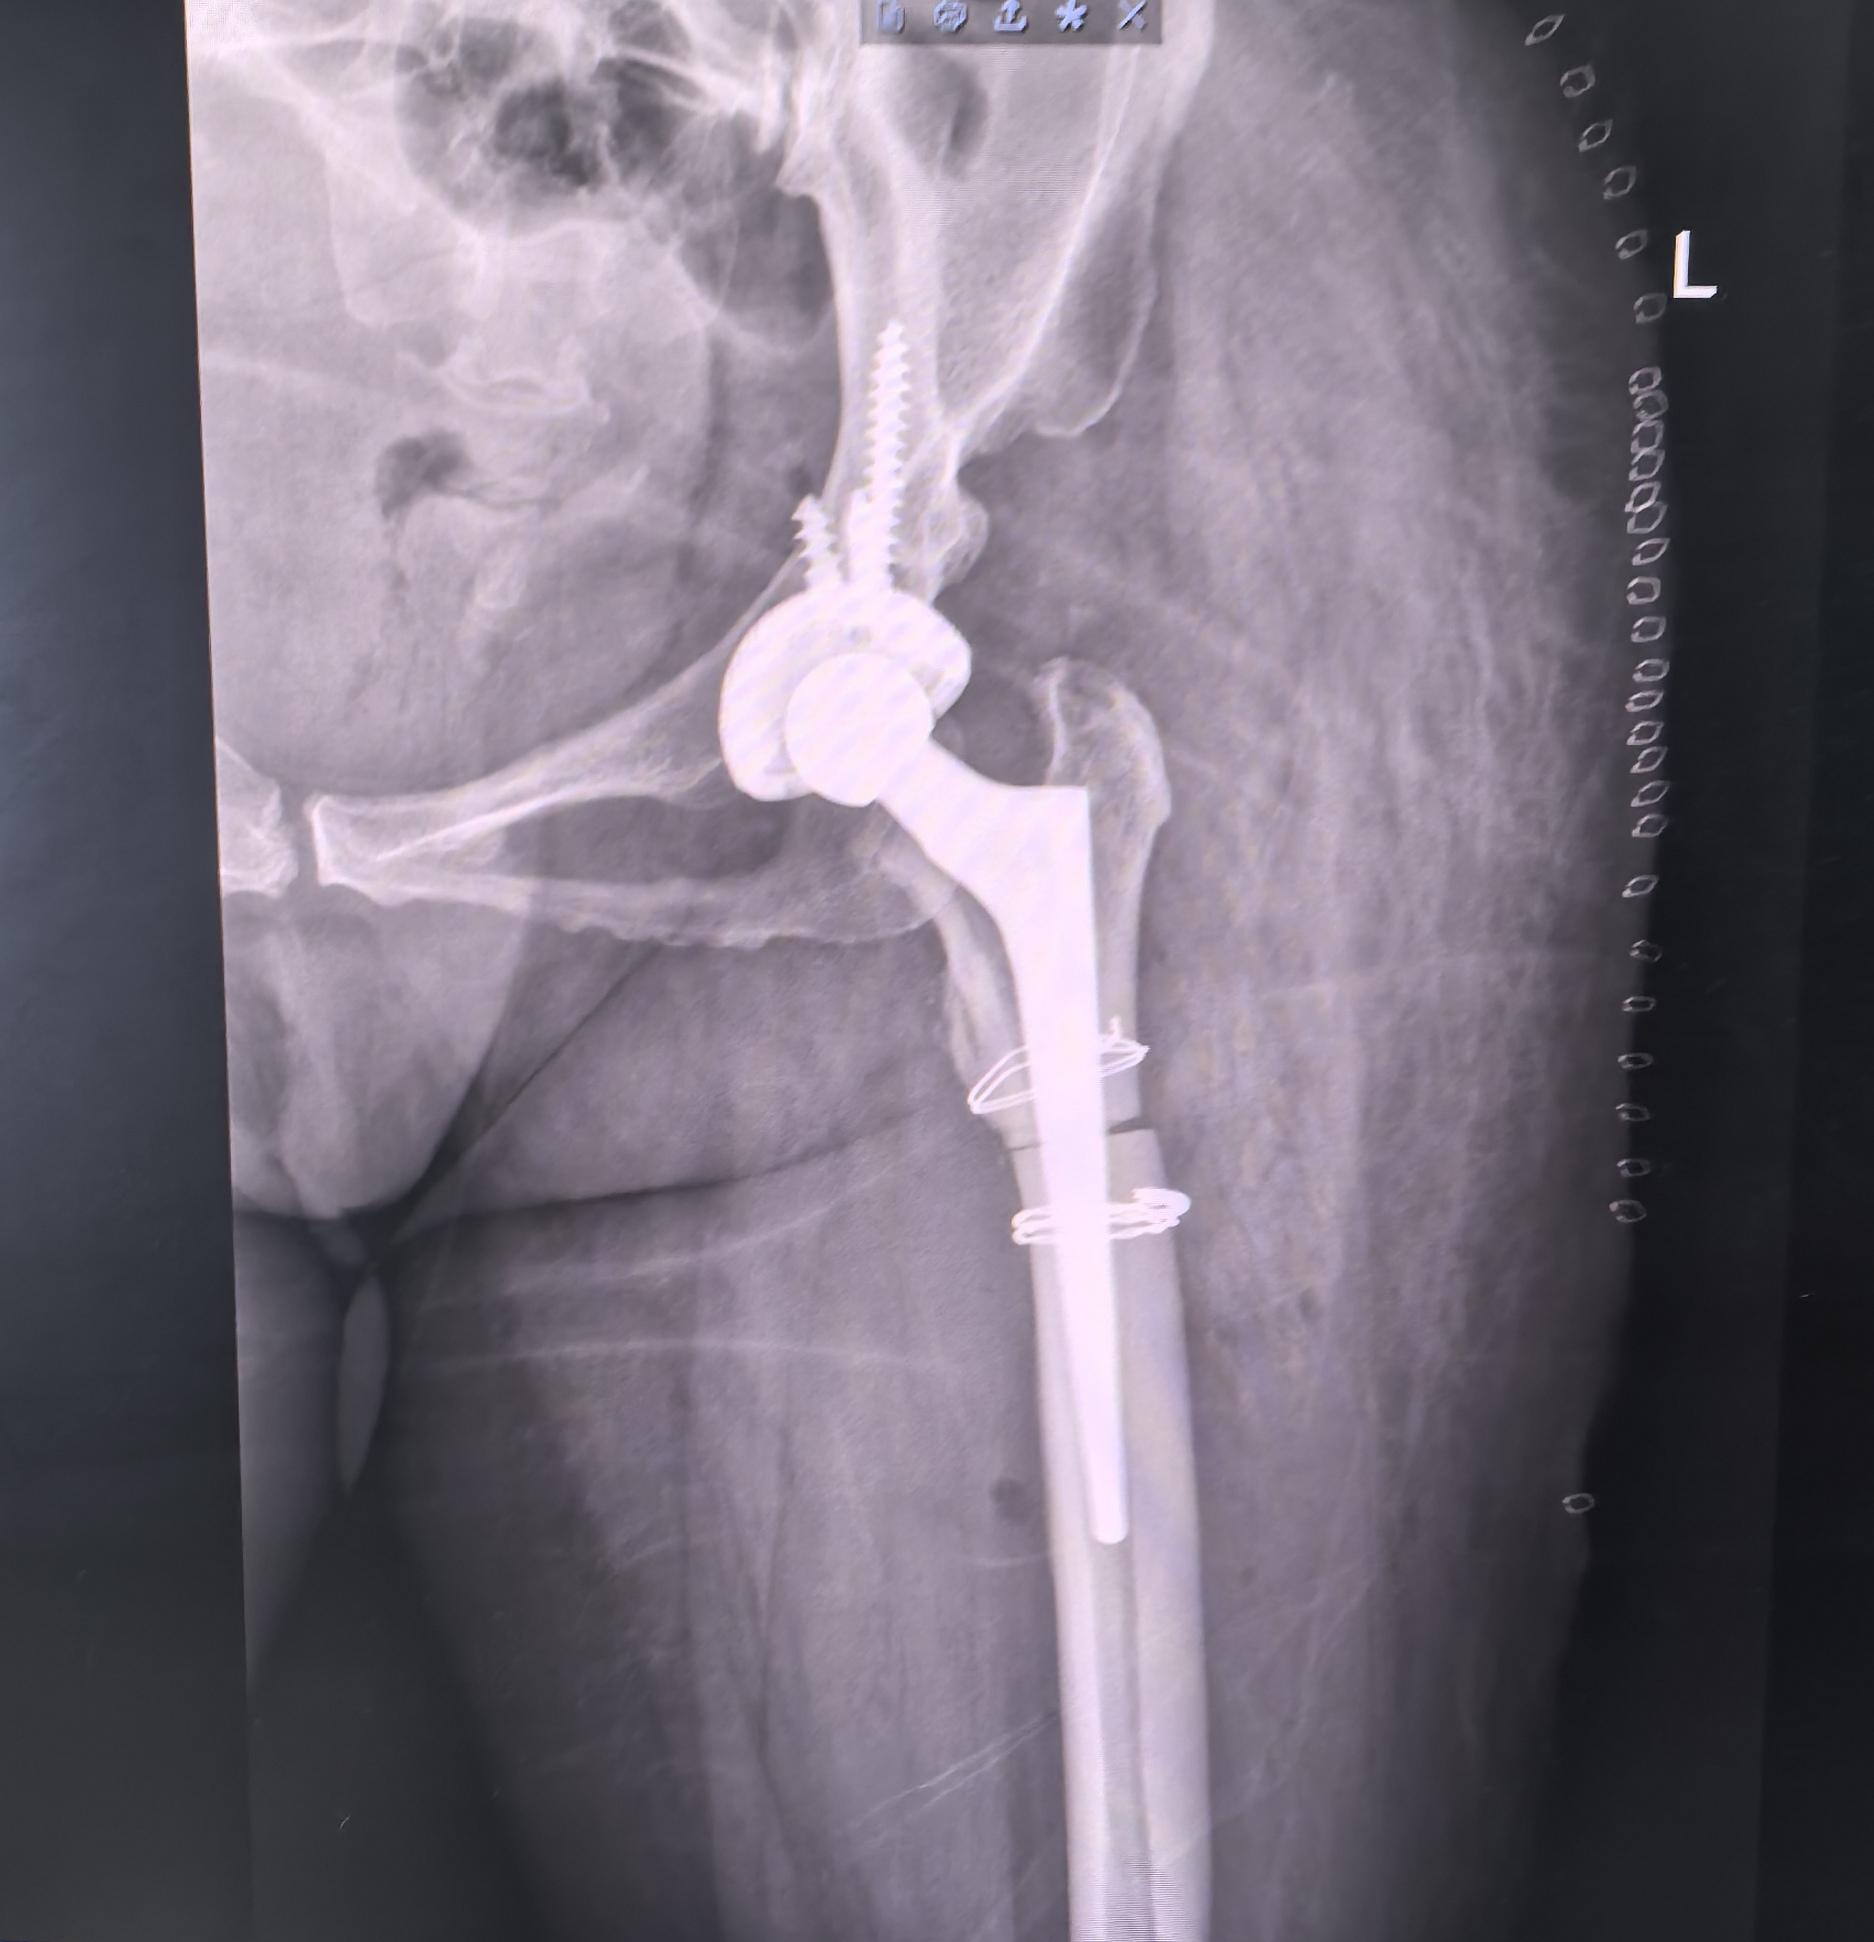

DDH先髋,高难度。DDH Crowe IV型,高难度手术,半个骨盆发育都不好,真臼25mm,髓腔直径5mm,术前患侧短4cm,术后等长,无神经症状,2天拄拐下床行走。愿每一位先髋患者都能得到有效的治疗,早日恢复正常生活🌹